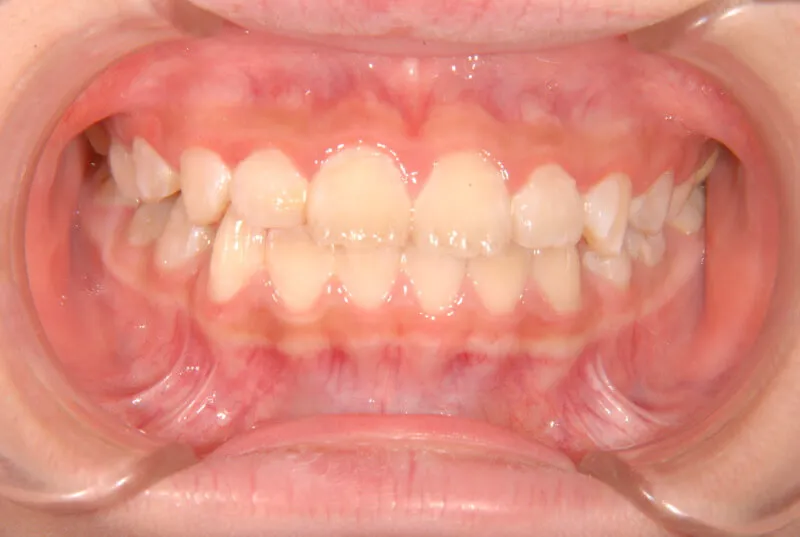

| 初診時年齢 | 小学校1年生(女性) | 主訴 | 受け口 | ||

| 診断名 | 叢生・反対咬合 | 装置名 | 拡大床 | ||

| 抜歯の有無 | 非抜歯 | 治療期間・通院回数 | 2年7ヶ月・21回 | ||

| 費用 | 481,890円(税込) | 費用内訳 | 相談料:1,050円 検査料:46,200円 施術料:210, 000円 装置料:105,000円 保定装置料:52,500円 調整料:3,150円×10回=31,500円 以上 消費税率5% / 調整料:3,240円×11回=35,640円 以上 消費税率8% | ブラケット・ ワイヤー |

付けずに治した |

| 特徴 |

固い食べ物が嫌い 乳歯列が綺麗に並んでいる ゆがんで生えている よく噛まないで飲み込む |

| 状態 |

永久歯が生える隙間がない(叢生) 受け口(口元が出ている/下顎前突/反対咬合) |

| リスク・副作用 |

矯正歯科治療に伴う一般的なリスク・副作用

|